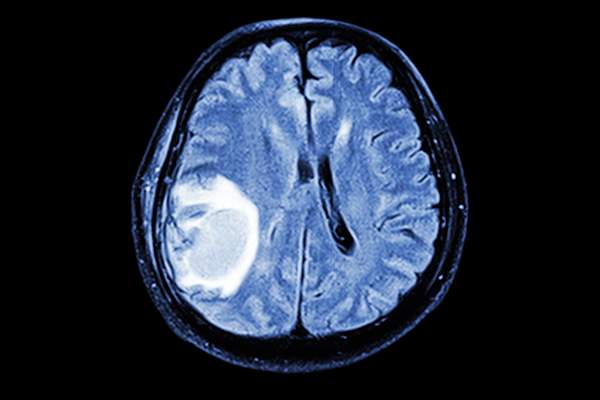

脑转移的风险

脑转移的迹象

症状可能包括身体上的和心理上的,可能包括:

- 逐渐加重的头痛和头部压力

- 模糊或重视

- 癫痫发作

- 呕吐和恶心

- 说话困难,包括说话含糊不清

- 行为、情绪或性格的变化

- 脊柱或大脑的核磁共振成像